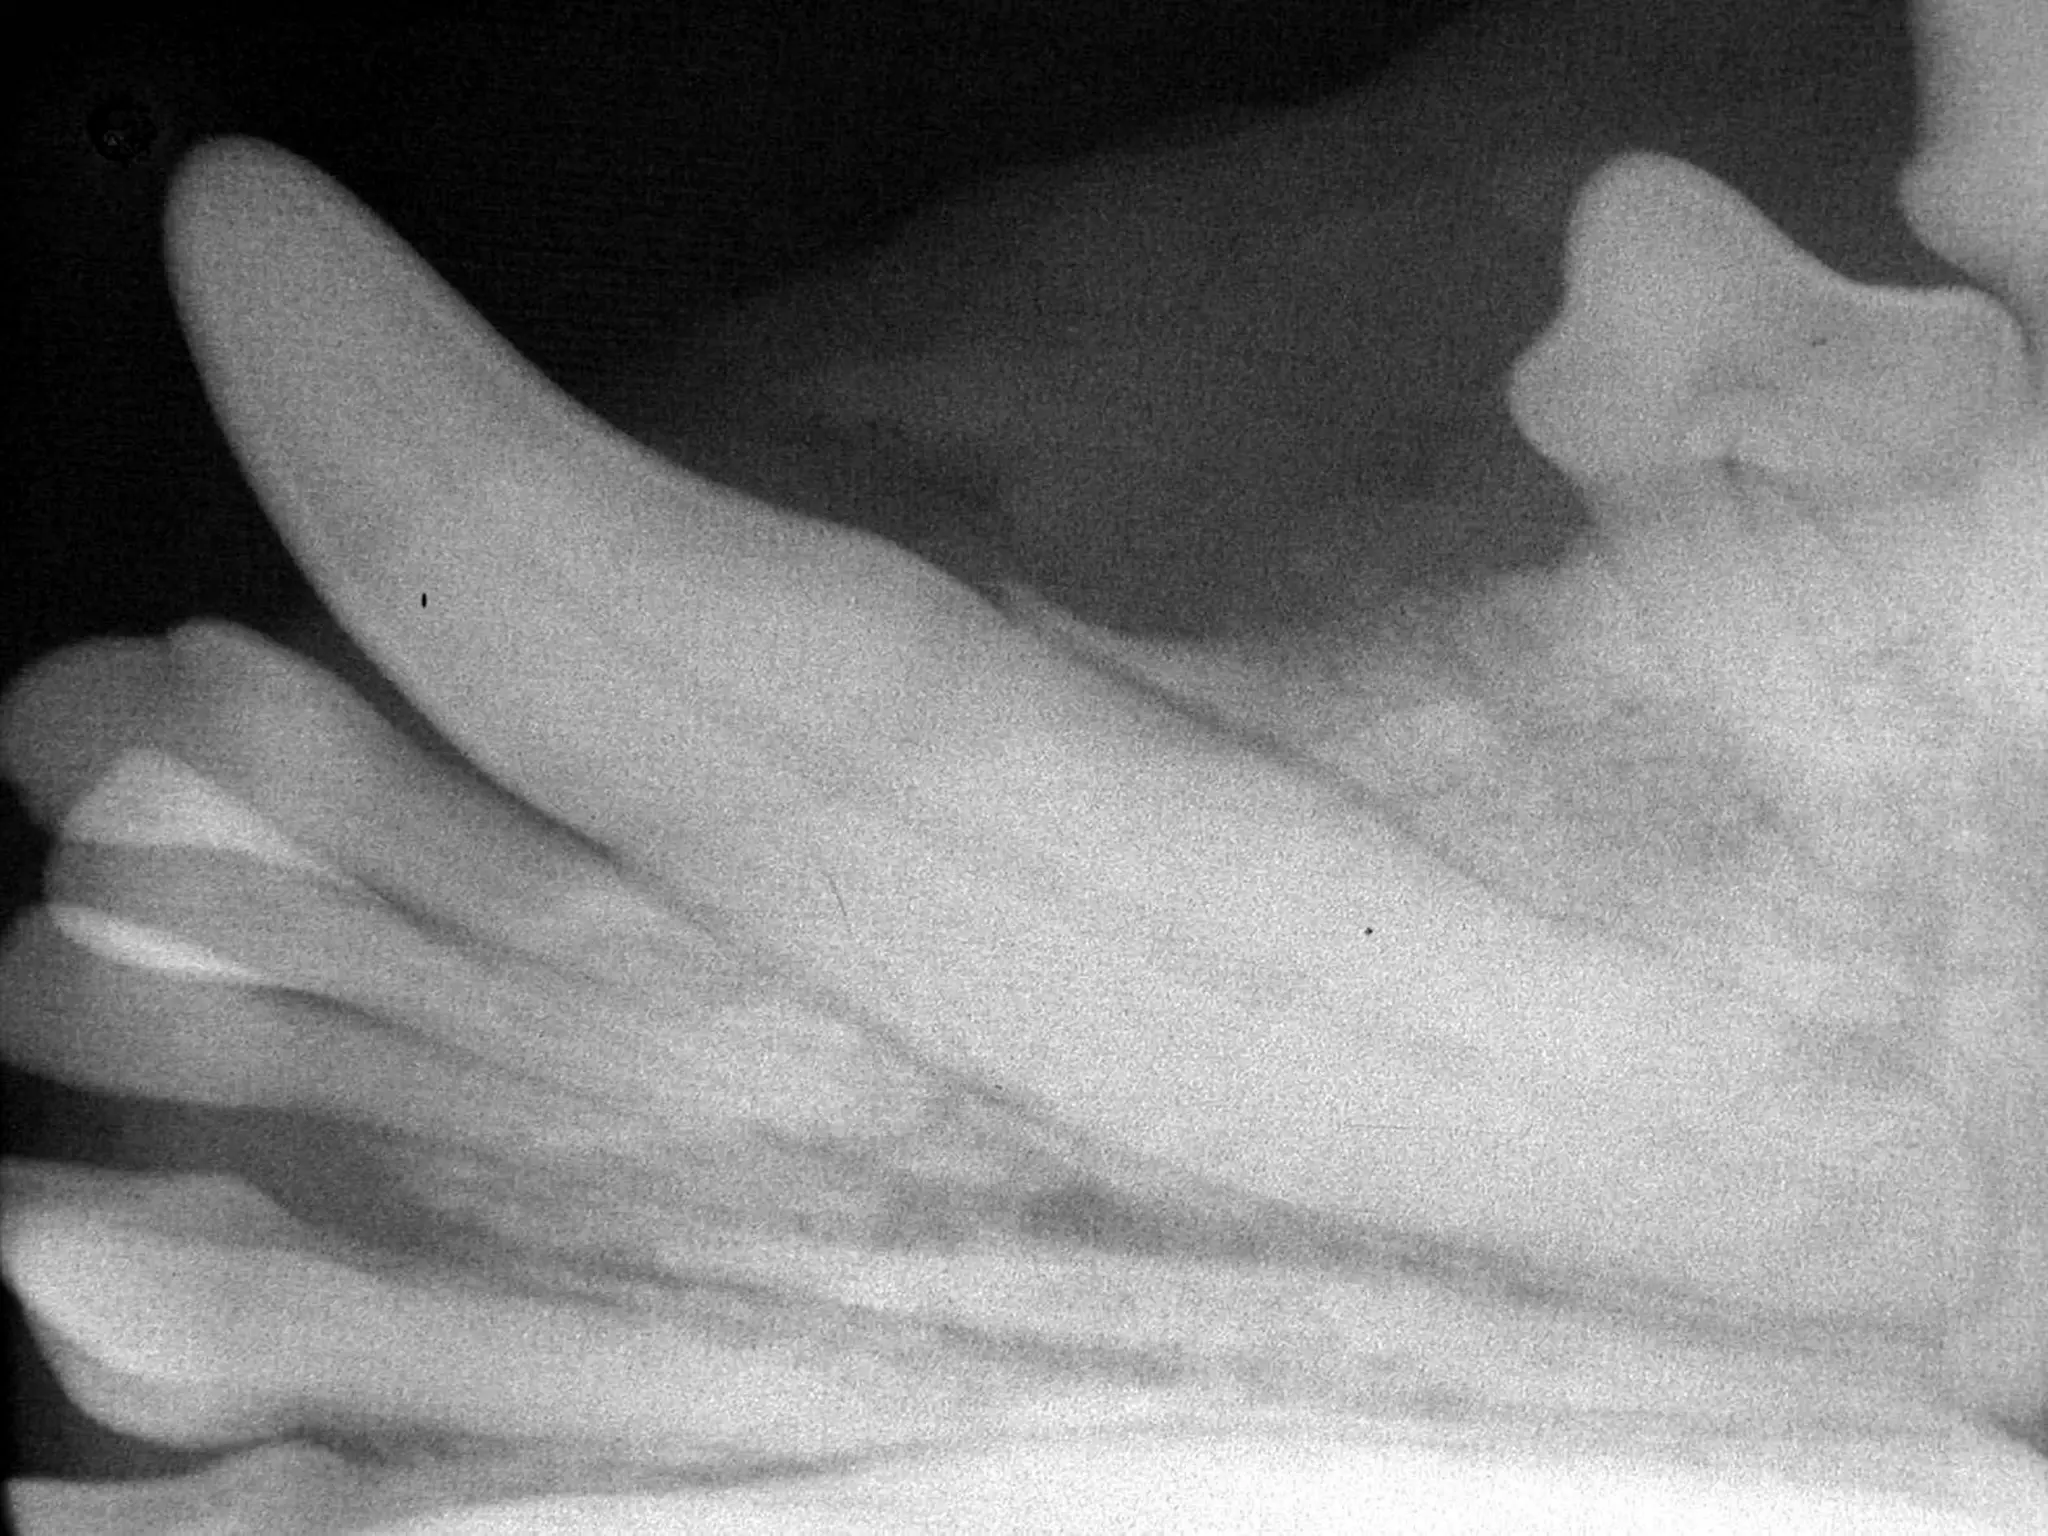

What is the disease present here?

Anatomical description of the

affected tooth?

• 38.

What is thedisease present here? Anatomical description of the affected tooth? 38